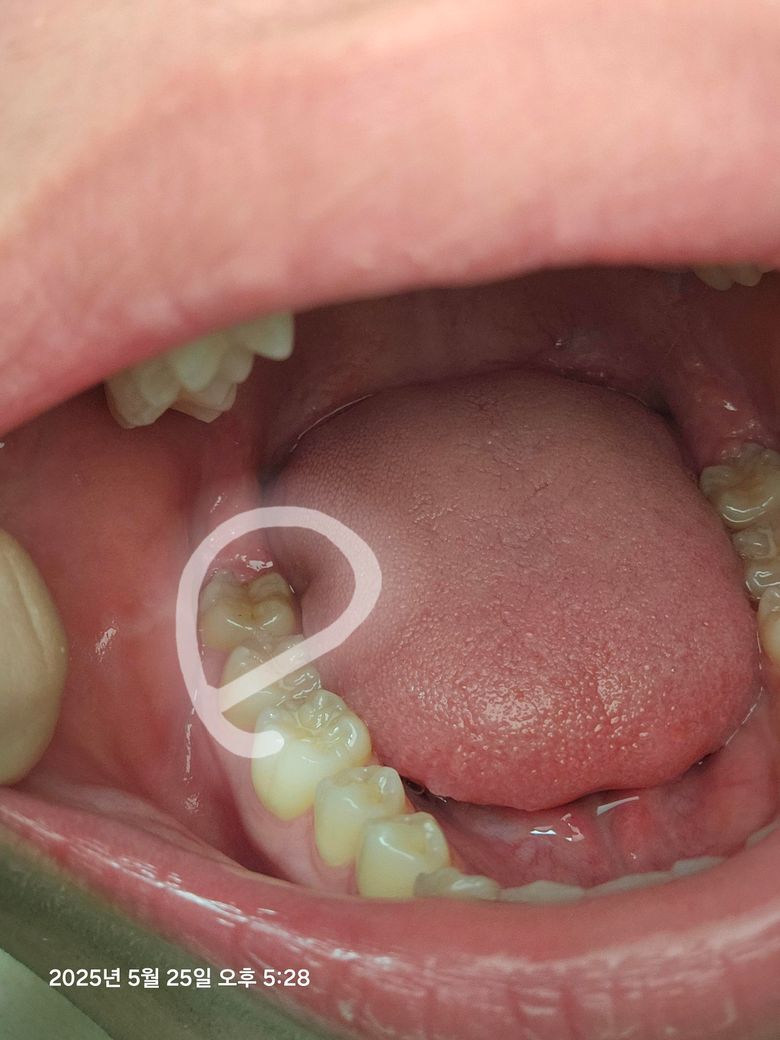

이빨에 작은 검은 점이 생겼어요.. 충치일까요?

이빨 안쪽에 보니까 진짜 작은 검은 점이 콕 하나 있더라구요... 그래서 뭐 음식물이 낀건가 싶어서 양치를 해봐도 안없어 지더라구요... 충치일까요? 어떻게 해야할가요?

이빨 안쪽에 보니까 진짜 작은 검은 점이 콕 하나 있더라구요... 그래서 뭐 음식물이 낀건가 싶어서 양치를 해봐도 안없어 지더라구요... 충치일까요? 어떻게 해야할가요? -> 충치 아닌거 같습니다

사진으로 봤을 경우에는 크게 충치가 있어 보이진 않습니다. 작은 충치의 경우에는 관리를 잘 하면 진행되지 않는 경우도 있습니다.

사진에 보이는건 초기 충치인거 같습니다. 그리고 사랑니 부위라 치료를 할 필요는 없고 관리만 잘하시면될것같습니다.